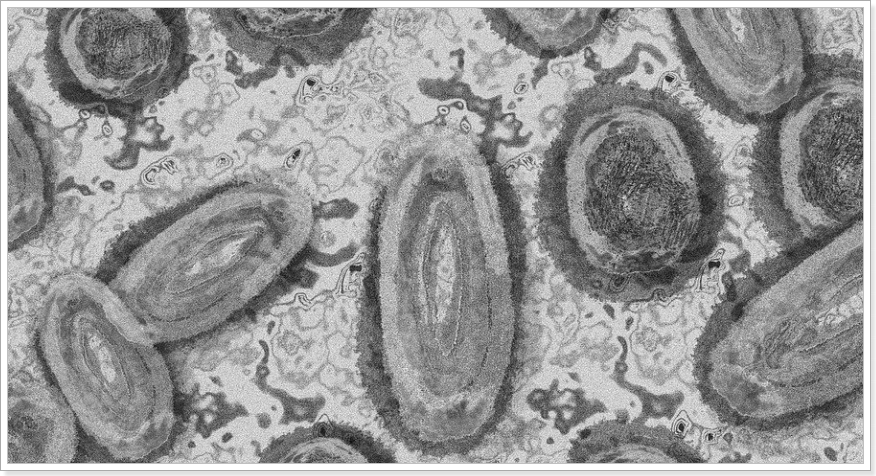

추가접종은 기초접종(1,2차) 및 추가접종(3,4차) 백신의 종류에 관계없이 mRNA 2가 백신을 우선적으로 권고하고 있습니다. 2가 백신은 방역상황 및 백신 수급상황을 고려하여 우선순위에 따른 접종을 시행중이네요. 2가백신은 초기에 유행한 바이러스와 변이 바이러스(오미크론 BA.1 또는 BA.4-5)에 대하여 항원을 만드는 백신인데요.

mRNA를 주성분으로 하고 있네요. 2가 백신의 장점은 기존 백신에서 확인된 중증 사망예방 효과는 지속하면서 최근에 유행하는 변이 바이러스에 대한 감염 예방 효과까지 가지고 있는 백신입니다. 다만 백신을 맞을 경우 4차 접종일부터 4개월 후에 접종 가능합니다.

그래프를 보면 2가 백신은 기존 백신보다 초기주에서 조금 더 효과가 좋았고, 4주 후에는 더 높은 중화능(바이러스를 무력화 하는 능력)을 보였습니다.